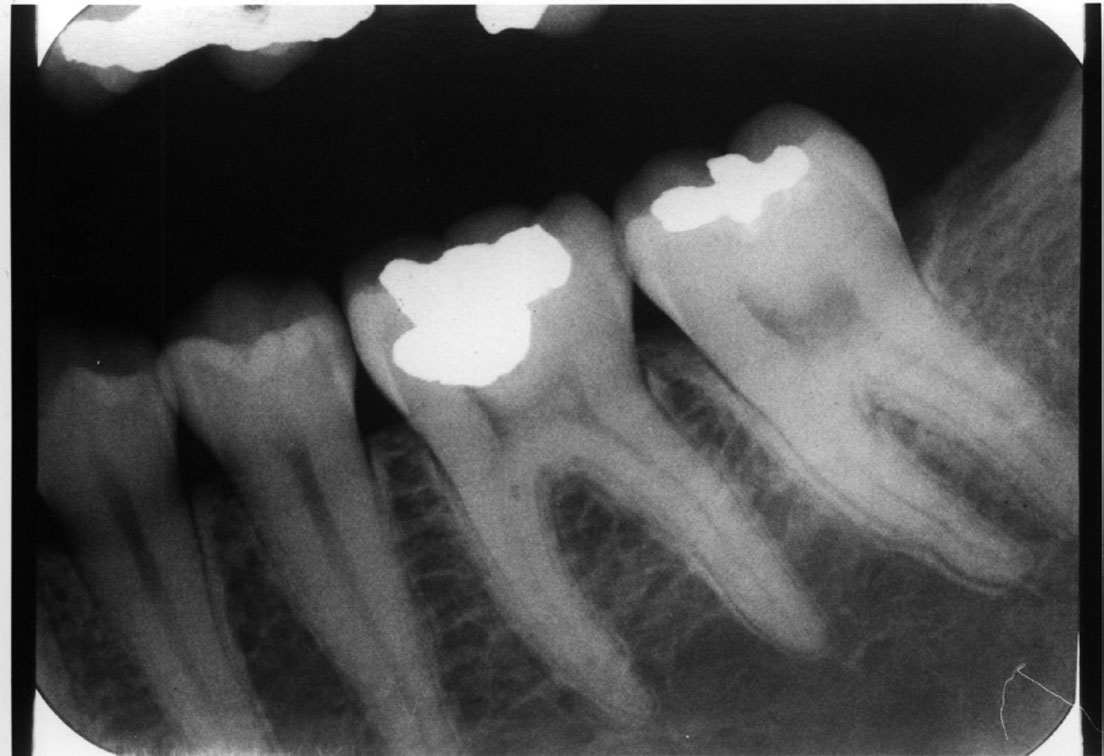

6. Vertical-Horizontal film placement errors: It is possible to misalign the film so that it is incorrect on both positions, compounding the effects of the individual positioning errors. Figure 7 is a radiograph which resulted from the film being positioned too far posteriorly in the horizontal position and too high in the vertical position. Notice that due to these placement errors, the mesial surface of the first mandibular premolar and the apices of the first and second mandibular premolars are not recorded.

Figure 7. Vertical horizontal film placement error.

Figure 7